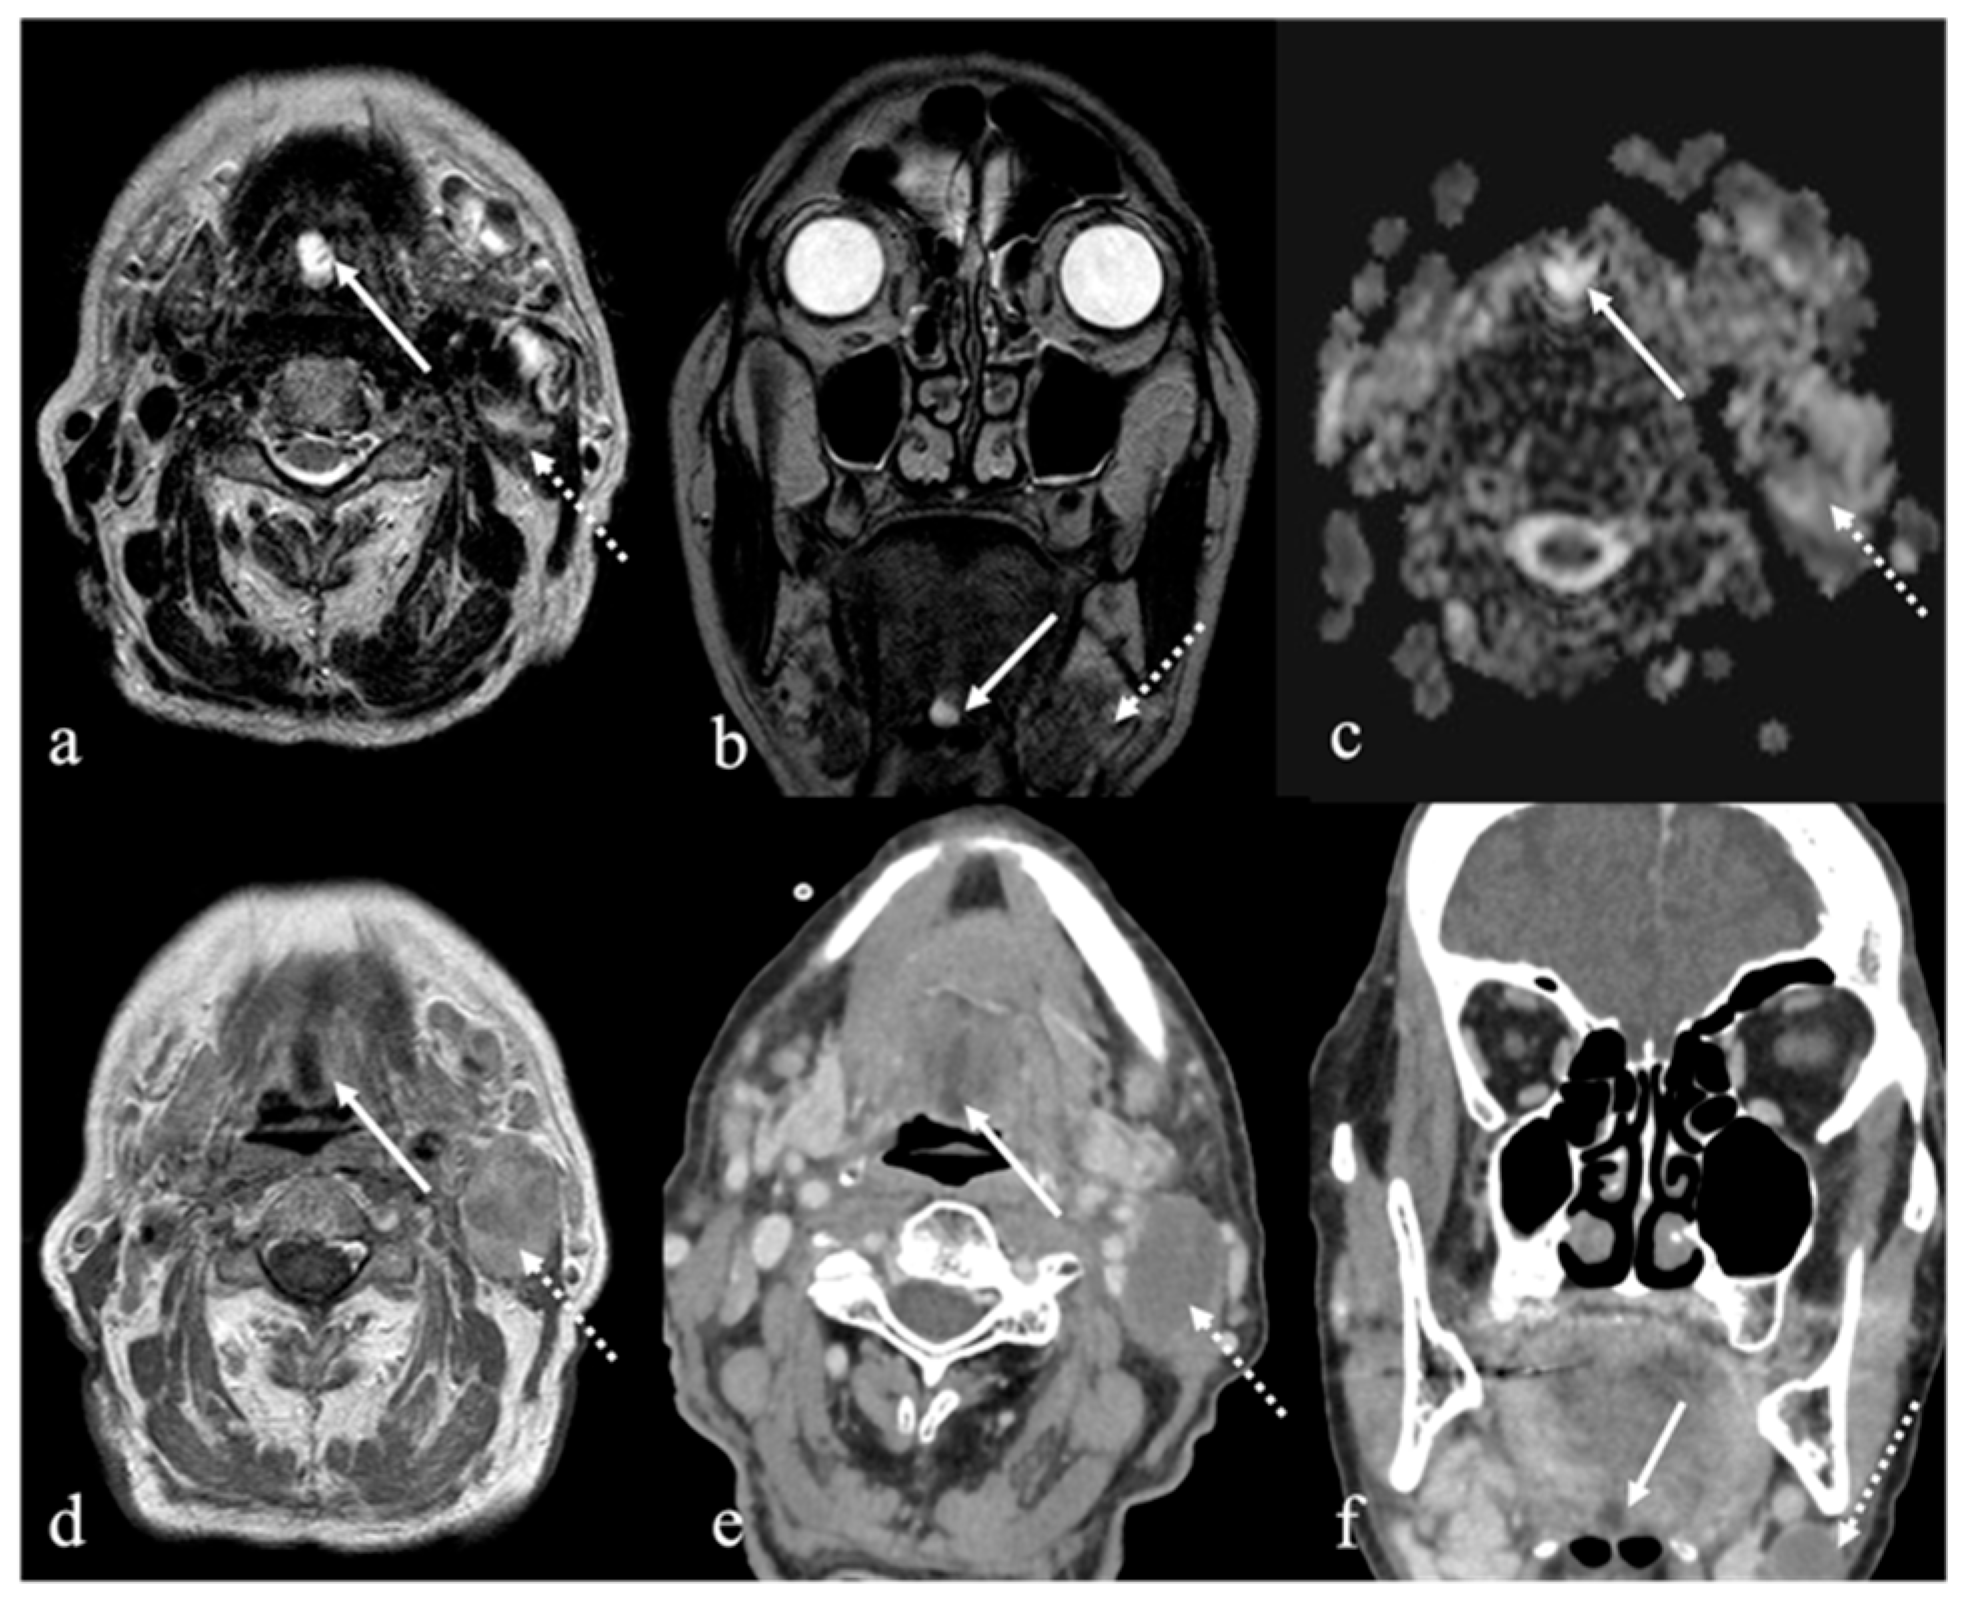

3. Schwannoma

5. Vascular Malformations and Tumors

5.1. Venous Malformations

| Schwannoma [6,7] | CT: hypodense MRI: high T2 SI, split fat, target and fascicular signs | Venous malformation, dermoid cysts, lipoma |

| Venous malformation [1,9] | CT: phleboliths MRI: high T2 SI, +CE | Other vascular malformations, schwannoma, dermoid cysts |